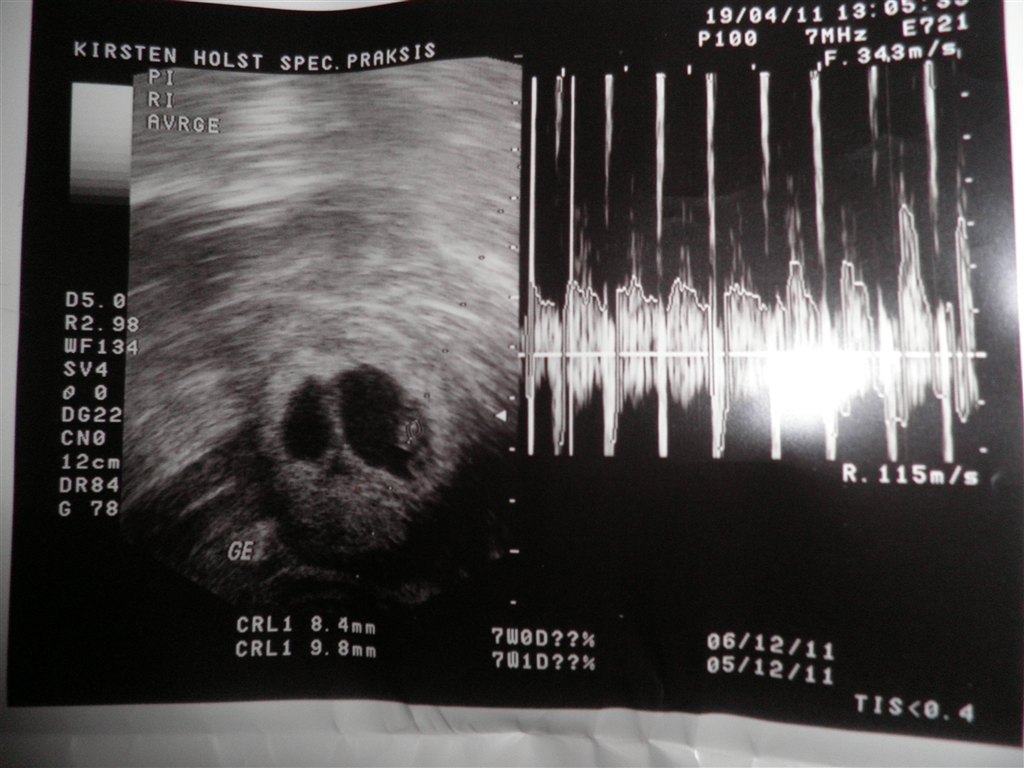

Tillykke, det ligner godt nok meget det billed jeg har fra min tryghedsscanning

Glæder mig til, at høre mere. Spørg endelig, hvis det er tveæggende (som jeg tror, synes det ligner meget min scanning) så kender jeg rimelig godt til graviditets forløbet.